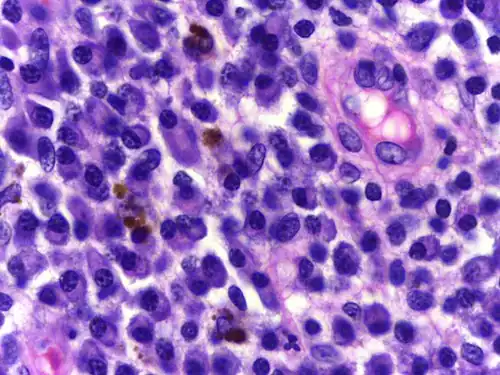

Plasmacellen[1] of plasmocyten[1] zijn immunoglobuline producerende witte bloedcellen, die ontstaan zijn uit B-lymfocyten. Plasmacellen worden gekenmerkt door:

- een grote hoeveelheid cytoplasma,

- een excentrisch gelegen celkern die een radstructuur vertoont,

- en met daaromheen een perinucleair, optisch leeg 'hofje'.